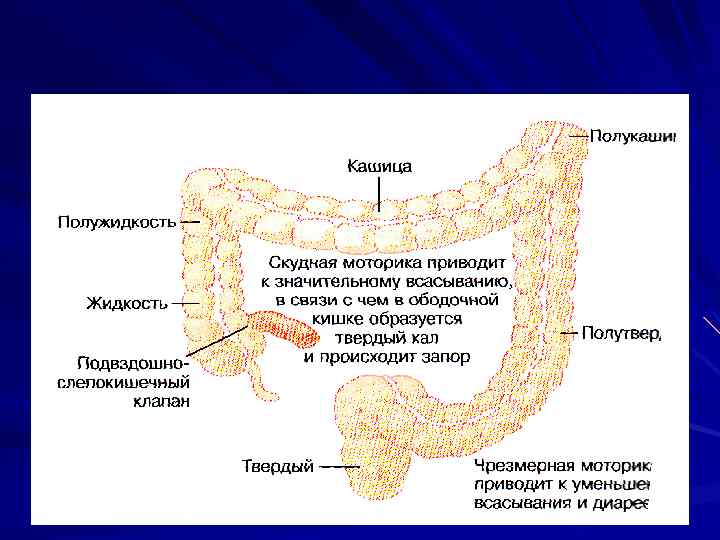

V МОТОРИКА ТОЛСТОЙ КИШКИ

V МОТОРИКА ТОЛСТОЙ КИШКИ

ФУНКЦИИ ВСАСЫВАНИЕ ВОДЫ И ЭЛЕКТРОЛИТОВ ХРАНЕНИЕ КАЛА t = 8 – 15 ч

ФУНКЦИИ ВСАСЫВАНИЕ ВОДЫ И ЭЛЕКТРОЛИТОВ ХРАНЕНИЕ КАЛА t = 8 – 15 ч

ДВИЖЕНИЯ ПЕРЕМЕШИВАЮЩИЕ – ГАУСТРАЦИИ ПРОПУЛЬСИВНЫЕ (ФОРСИРОВАННЫЕ)

ДВИЖЕНИЯ ПЕРЕМЕШИВАЮЩИЕ – ГАУСТРАЦИИ ПРОПУЛЬСИВНЫЕ (ФОРСИРОВАННЫЕ)

ФОРСИРОВАННЫЕ ДВИЖЕНИЯ КАЖДОЕ = 2 – 3 мин СЕРИИ по 10 – 30 мин ВСЕГО 1– 3 в сутки

ИЛЕОЦЕКАЛЬНЫЙ КЛАПАН ЗАДЕРЖКА ХИМУСА СПОСОБСТВУЕТ ВСАСЫВАНИЮ В ТОЛСТУЮ КИШКУ ПРОХОДИТ ХИМУСА 1. 5 – 2. 0 л/сут

ИЛЕОЦЕКАЛЬНЫЙ КЛАПАН ЗАДЕРЖКА ХИМУСА СПОСОБСТВУЕТ ВСАСЫВАНИЮ В ТОЛСТУЮ КИШКУ ПРОХОДИТ ХИМУСА 1. 5 – 2. 0 л/сут